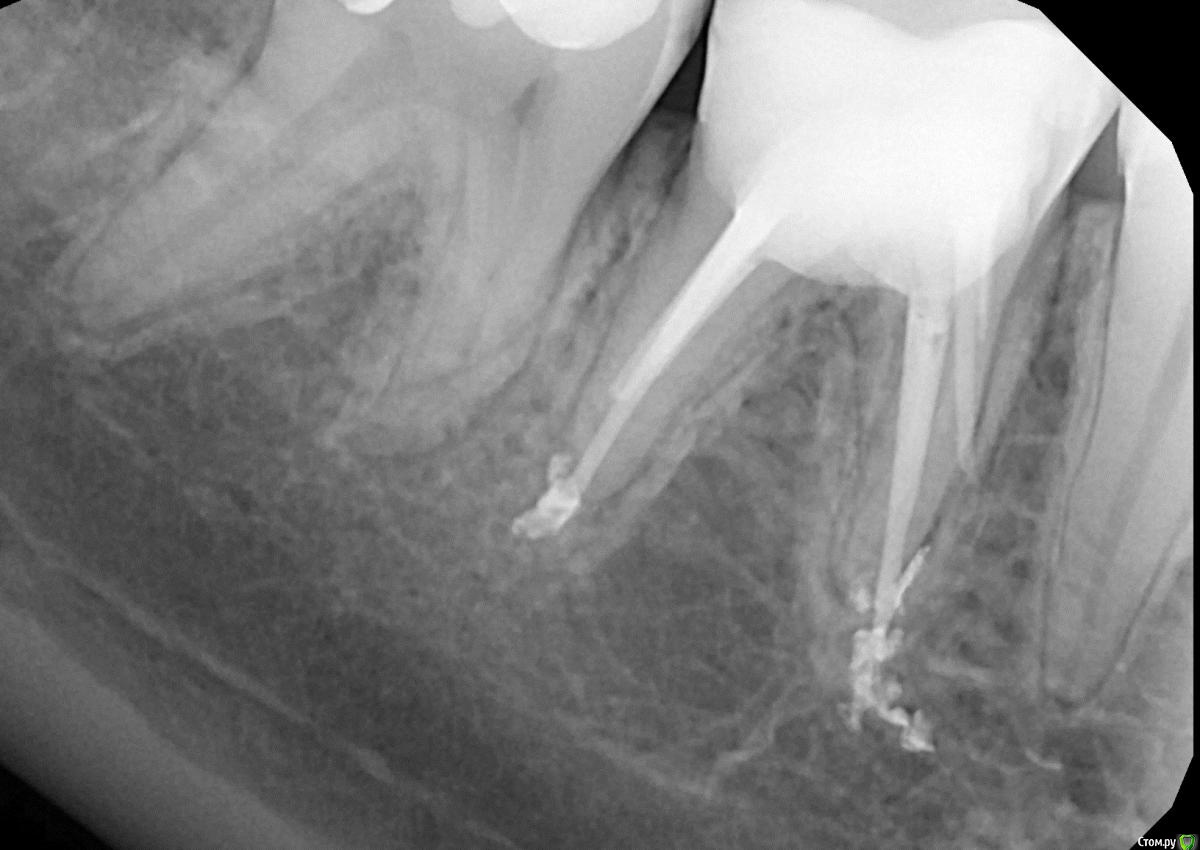

Peda Опубликовано 29 октября, 2015 Автор Поделиться Опубликовано 29 октября, 2015 Прошу оценить качество лечения Ссылка на комментарий

сирена Опубликовано 30 октября, 2015 Поделиться Опубликовано 30 октября, 2015 К качеству лечения есть вопросы,но никакой катастрофы не вижу.Если не беспокоит,пусть стоИт,может и больше пяти лет протянет(раз в год желательно прицельный снимок делать).Если треснет,почувствуете боль при накусывании.Сможете показать снимок ДО перелечивания?Очень интересно. Ссылка на комментарий

Peda Опубликовано 2 ноября, 2015 Автор Поделиться Опубликовано 2 ноября, 2015 Похоже он того...Сначала пульсировал изнутри, а потом стал побаливать при нажатии языком и при надкусывание еды, например хлеба. Причем то болит сильнее, то не очень. Вобщем глупая затея была. Заплатил в 2 раза больше чем в первый раз и одни мучения. Гарантии нет, а эксперимент не удался. Даже месяца без проблем не простоял.Вот снимок до, качество плохое так как фотографировал с пленки. Ссылка на комментарий

сирена Опубликовано 3 ноября, 2015 Поделиться Опубликовано 3 ноября, 2015 Спасибо.Не столько там проблем,сколько было критики.Ну,если беспокоит,ничего не попишешь - удаляйте. Ссылка на комментарий

Peda Опубликовано 16 января, 2016 Автор Поделиться Опубликовано 16 января, 2016 Если кому интересно...Фото спустя 3 месяца после перфорации.Неприятные ощущения прошли, зуб ощущается как свой, а не инородное тело.Вроде воспаления на снимке нет?!http://s019.radikal.ru/i623/1601/79/b905a1798917.jpg Ссылка на комментарий

Zlata-doctor Опубликовано 20 января, 2016 Поделиться Опубликовано 20 января, 2016 За три месяца скорее всего и не будет изменений.Могу порекомендовать повторить рентген через год, а в дальнейшем делать раз в год-два снимок ( при отсутствии симптомов воспаления). И действовать по ситуации. В данный момент ваш асимптоматичный зуб с удовлетворительной рентгенологической картиной срочного удаления не требует. 1 Ссылка на комментарий